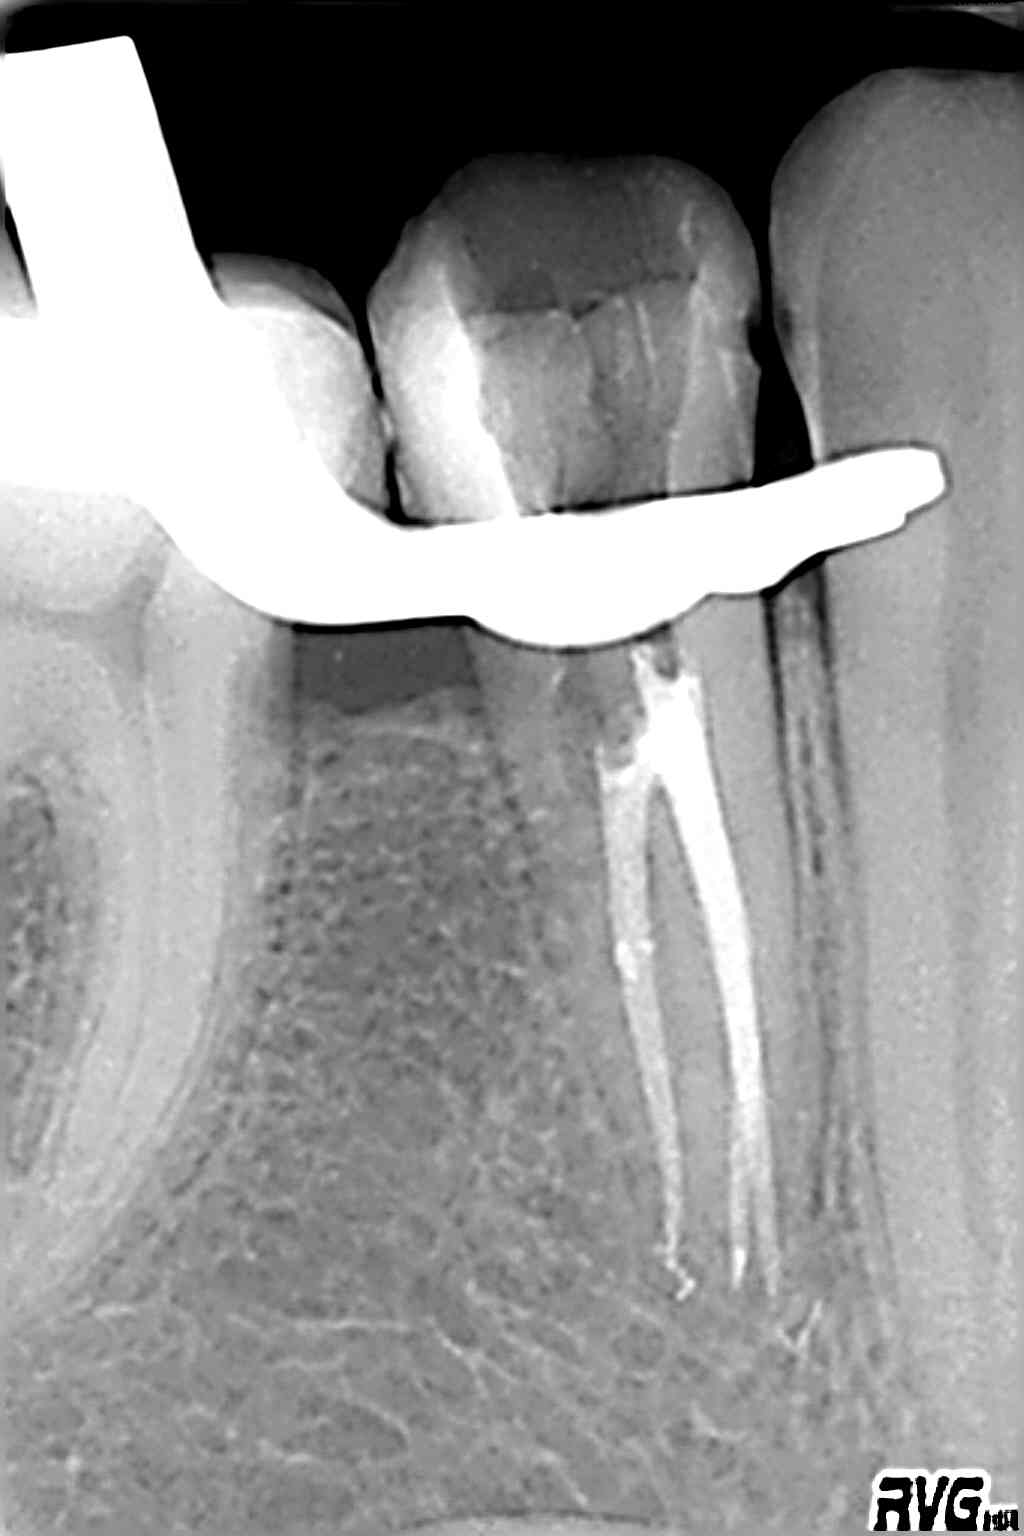

Radiowizjografia jest podstawowym narzędziem do diagnostyki, oraz kontrolowania przeprowadzonego zabiegu stomatologicznego.

Takie dziedziny stomatologii jak implantologia czy endodoncja nie mogłyby być skutecznie wykonywane bez cyfrowych systemów radiologicznych.

W odroznieniu od standardowego RTG, radiowizjografia eliminuje tradycyjną kliszę rentgenowską, która zostaje zastąpiona specjalnym czujnikiem, dzieki któremu od razu uzyskujemy wysokiej jakości obraz na ekranie komputera. Technika cyfrowa dzięki możliwości zastosowania kontrastu, powiększenia wybranego fragmentu obrazu, dokonywania pomiarów pozwala na nieporównywalnie dokładniejszą ocenę sytuacji klinicznej niż tradycyjne zdjęcie RTG.

Radiowizjografia pozwala obniżyć dziesięciokrotnie dawkę promieniowania w stomatologicznych zdjęciach wewnątrzustnych w porownaniu z standardowymi zdjęciami wykonanymi na kliszy.

Dzięki łatwości archiwizacji i dostępu do danych mamy możliwość analizowania efektów leczenia i kontroli stanu uzębienia na przestrzeni wielu lat.